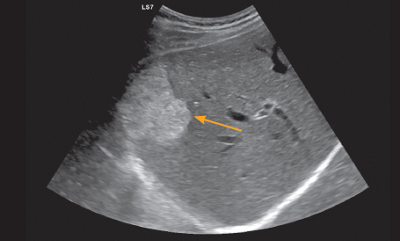

Der Leber-Ultraschall zeigt ein gutartiges Hämangiom (Blutschwamm).

Bei einem 62-jährigen Patienten wird im Ultraschall zufällig ein 4 cm grosser Knoten in der Leber entdeckt. Er wird zu einem auf Lebererkrankungen spezialisierten Gastroenterologen überwiesen, der mittels kontrastmittelverstärkten Ultraschalls ein Hämangiom (Blutschwamm) diagnostiziert (vgl. Abb. 1). Aufgrund der Gutartigkeit wird der Leberknoten belassen, eine Therapie ist nicht erforderlich. In einem vergleichbaren Fall wird bei einer 70-jährigen Frau in der Bauchspeicheldrüse ein 2 cm grosser Knoten nachgewiesen. Der Gastroenterologe diagnostiziert mittels Endosonographie (Ultraschall mittels Sonde über den Magen) und endosonographischer Punktion (Gewebeentnahme) einen neuroendokrinen Tumor (vgl. Tabelle 1). Die Patientin wird mit dem Ziel der Heilung operiert.